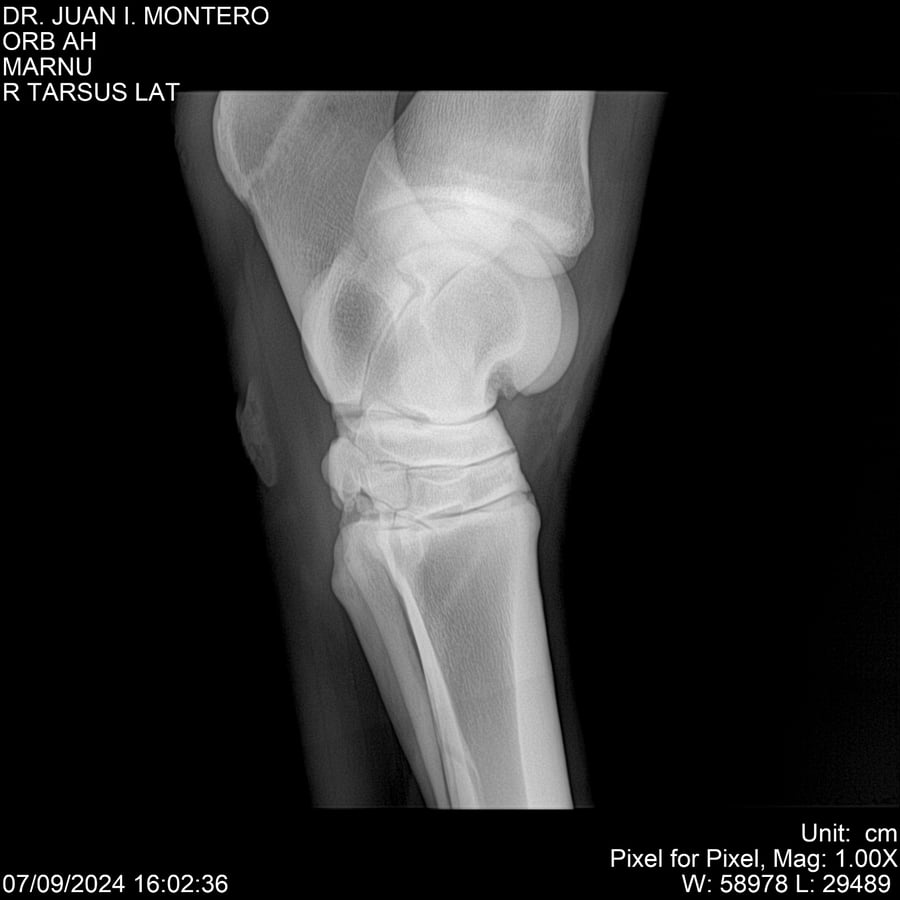

LOTE 21, ORB AH Lote Anterior Volver al remate Lote Siguiente Ficha Contacto Montevideo - Ficha del Lote Identificador: #282519 Categoría: Yeguarizos Montevideo - 57 Visualizaciones ClicData Contacto Empresa: Abelenda N. R., Walter Hugo Nombre*: Teléfono* : E-mail* : Mensaje Enviar Registrese gratis Este contenido Exclusivo está disponible sólo para usuarios registrados Ingresar